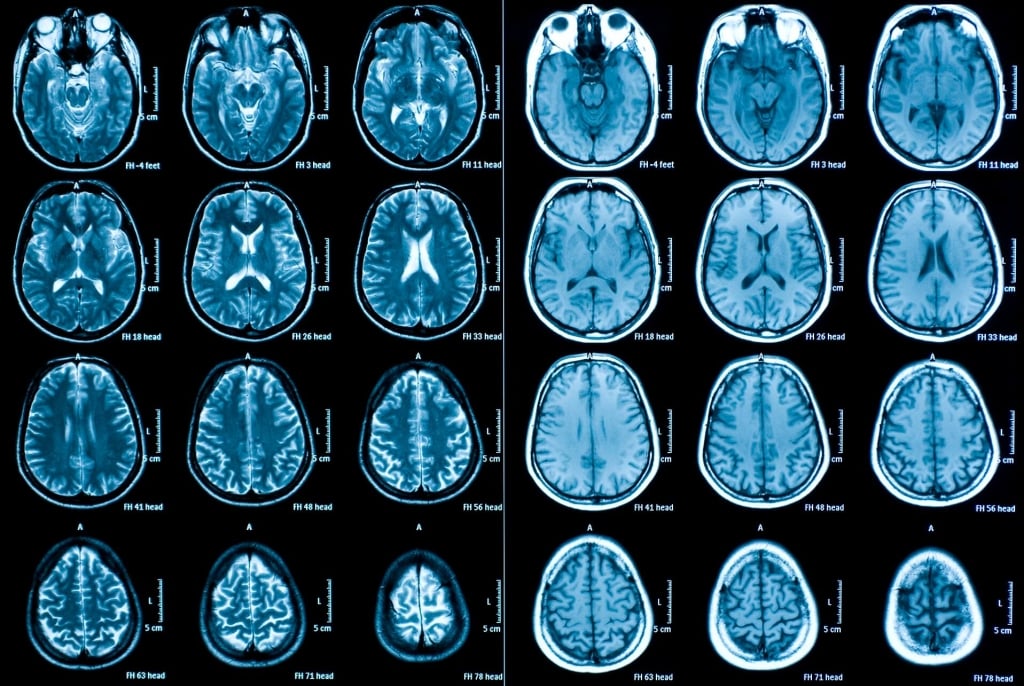

«Il potere che dà una collaborazione su larga scala e multicentrica ha permesso questo risultato in quanto studi longitudinali di neuroimaging sono ben difficili da condurre – è il commento di uno degli psichiatri del gruppo. – Così, mettendo insieme i dati di 14 laboratori sparsi nel mondo abbiamo ottenuto le più limpide immagini dell’impatto neurotossico del disturbo bipolare, soprattutto degli episodi maniacali». I ricercatori hanno riunito l’imaging da risonanza magnetica (Mri) e dettagliati dati clinici di 307 persone affette da disturbo bipolare messe a confronto con 925 persone sane (gruppo di controllo). I partecipanti son stati controllati a due traguardi situati da sei mesi a nove anni di distanza.

La scoperta più sorprendente è stato trovare che la corteccia, lo strato più esterno del cervello, si è assottigliata col tempo tanto più quanti più erano stati gli episodi maniacali vissuti. I cambiamenti erano più evidenti nella corteccia prefrontale, un’area associata al controllo esecutivo e alla regolazione emotiva. «Il fatto che l’assottigliamento corticale si verifichi in pazienti toccati da episodi maniacali sottolinea l’importanza di cure per prevenire questi attacchi e di una puntuale informazione degli psichiatri – ha commentato l’autore senior dello studio, professor Mikael Landén, docente all’Università di Gothenburg (Svezia). – I ricercatori dovrebbero concentrarsi per meglio capire i meccanismi progressivi messi in atto dal disturbo bipolare così da arrivare a opzioni terapeutiche migliori».

Rispetto al gruppo di controllo, le persone bipolari hanno mostrato anche un allargamento dei ventricoli cerebrali, cavità che contengono fluido cerebrospinale. Nelle aree corticali fuori della corteccia prefrontale, invece, i bipolari hanno evidenziato un più lento assottigliarsi in confronto ai partecipanti sani. Osserva il primo autore dello studio, lo svedese Chistoph Abé: «L’abnorme allargamento dei ventricoli e in particolare l’associazione tra l’assottigliarsi corticale e i sintomi maniacali indica che il disturbo bipolare sia in effetti un disturbo neuroprogressivo, il che spiegherebbe il peggioramento nel tempo dei disturbi maniacali in alcuni pazienti».